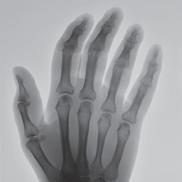

“One solution that we found is to use our Siemens MAGNETOM Free.Max 0.55T MRI Scanner,” says Dr. Seiberlich. As one of the few locations nationwide that owns and operates this “low field” machine, the MIITT team and UM Radiology have identified niche utilities, including the ability to conduct “in bore” biopsies--meaning the patient stays in the MRI scanner throughout the procedure. Now radiologists can clearly see the area that they want to biopsy, and accurately direct metallic needles without risk of damaging surrounding tissue. In addition to a wider bore, initially intended for larger patients or those with claustrophobia, the image quality of the scans is less affected by metal implants at low field strength. This is also advantageous when scanning patients with prior joint replacement surgery. “We can also capture MRI scans of parts of the body that are in motion, such as the heartbeat or blood flow,” she says. “Instead of a one second scan to make an image of a stationary body part, we can create a usable image in 20 milliseconds. We continue to discover special use cases that make this machine an exciting tool for us to have in radiology.”